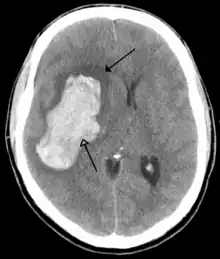

Brain tumours can be either benign or cancerous. Most malignant tumours arise from another part of the body, most commonly from the lung, breast and skin.[177] Cancers of brain tissue can also occur, and originate from any tissue in and around the brain. Meningioma, cancer of the meninges around the brain, is more common than cancers of brain tissue.[177] Cancers within the brain may cause symptoms related to their size or position, with symptoms including headache and nausea, or the gradual development of focal symptoms such as gradual difficulty seeing, swallowing, talking, or as a change of mood.[177] Cancers are in general investigated through the use of CT scans and MRI scans. A variety of other tests including blood tests and lumbar puncture may be used to investigate for the cause of the cancer and evaluate the type and stage of the cancer.[177] The corticosteroid dexamethasone is often given to decrease the swelling of brain tissue around a tumour. Surgery may be considered, however given the complex nature of many tumours or based on tumour stage or type, radiotherapy or chemotherapy may be considered more suitable.[177]

Some treatments for stroke are time-critical. These include clot dissolution or surgical removal of a clot for ischaemic strokes, and decompression for haemorrhagic strokes.[195][196] As stroke is time critical,[197] hospitals and even pre-hospital care of stroke involves expedited investigations – usually a CT scan to investigate for a haemorrhagic stroke and a CT or MR angiogram to evaluate arteries that supply the brain.[194] MRI scans, not as widely available, may be able to demonstrate the affected area of the brain more accurately, particularly with ischaemic stroke.[194]